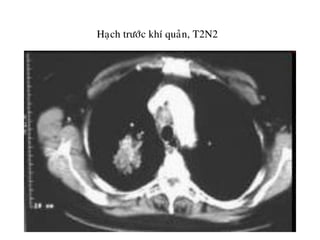

Haïch tröôùc khí quaûn, T2N2